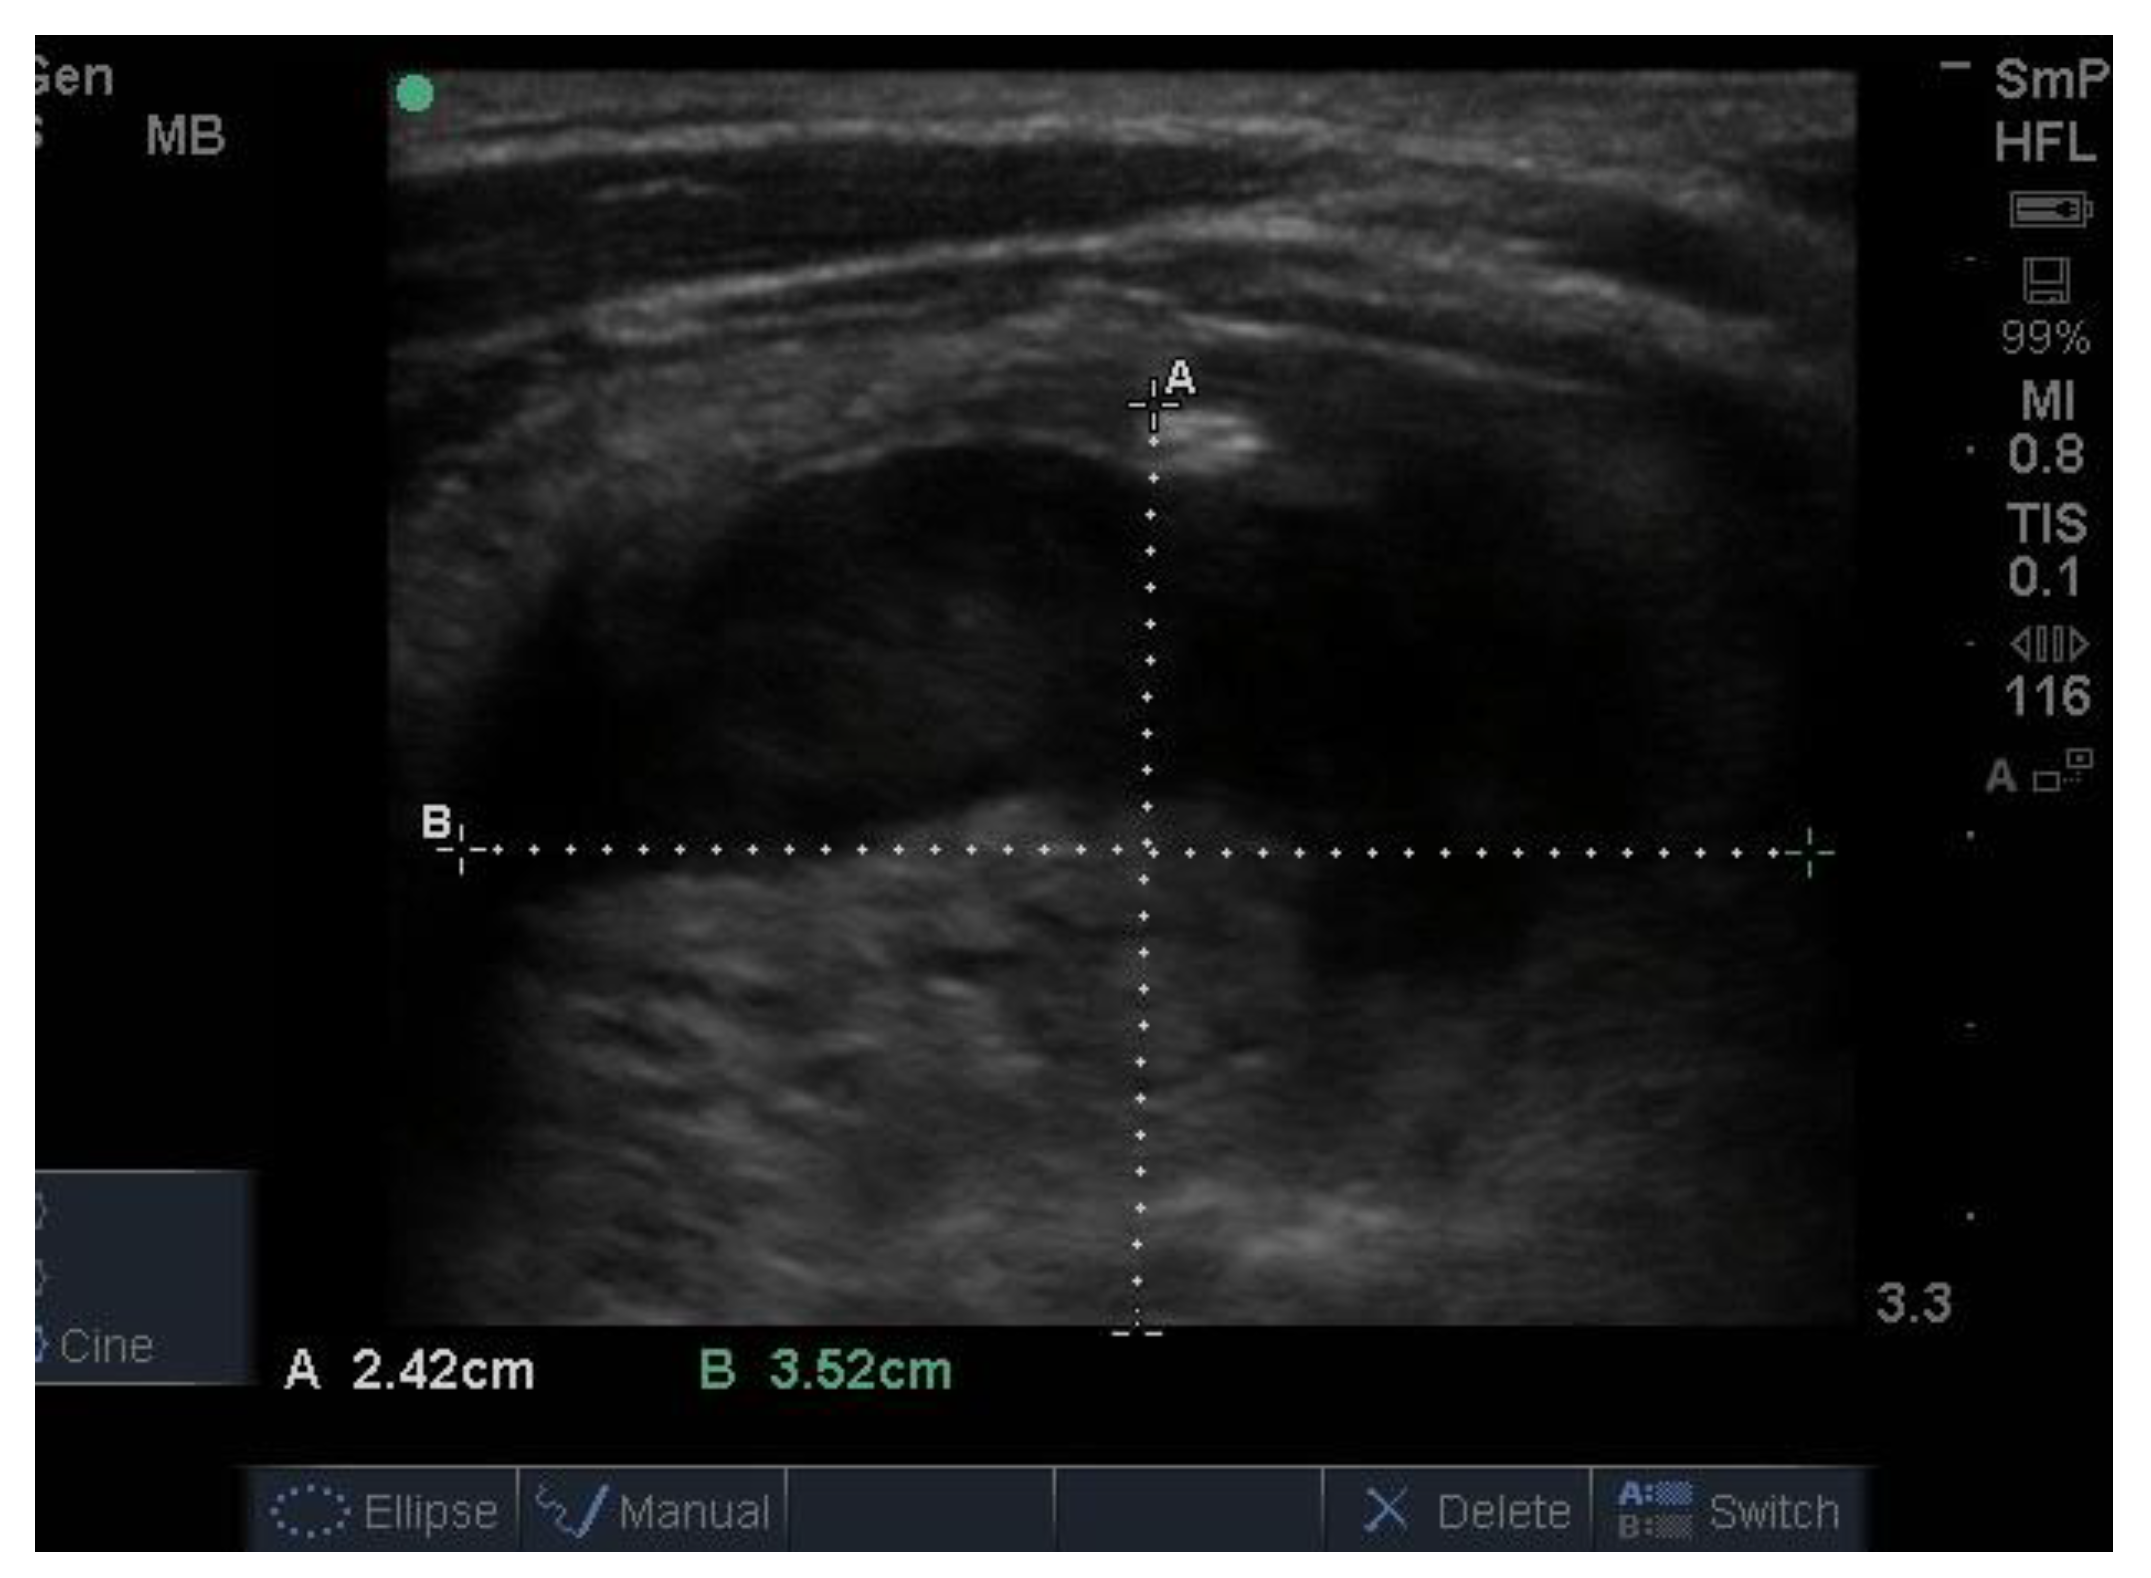

14. Parathyroid Disease

Because the senior author (JW) routinely measures serum calcium, parathyroid hormone (PTH) and vitamin D in his patients, hyperparathyroidism due to a benign adenoma of one of the parathyroid glands appears to be much more common than previously thought. The parathyroid glands are hidden behind the thyroid and so may be obscured by thyroid nodules, although they can often be seen in the longitudinal view below the lobes, as a hypoechoic lesion of around 1 cm in diameter (Figure 18).

The parathyroid adenoma is typically hypoechoic by comparison to the nearby thyroid tissue, which is consistent with the author’s experience. However, only about 50% of subsequently proven parathyroid adenomas are seen on ultrasound and even the Sestamibi nuclear scan fails to pick them up in about 30% of cases.

Figure 18. Thyroid ultrasound from a patient with hyperparathyroidism showing a hypoechoic lesion below the right thyroid lobe that was confirmed to be a parathyroid adenoma at surgery.